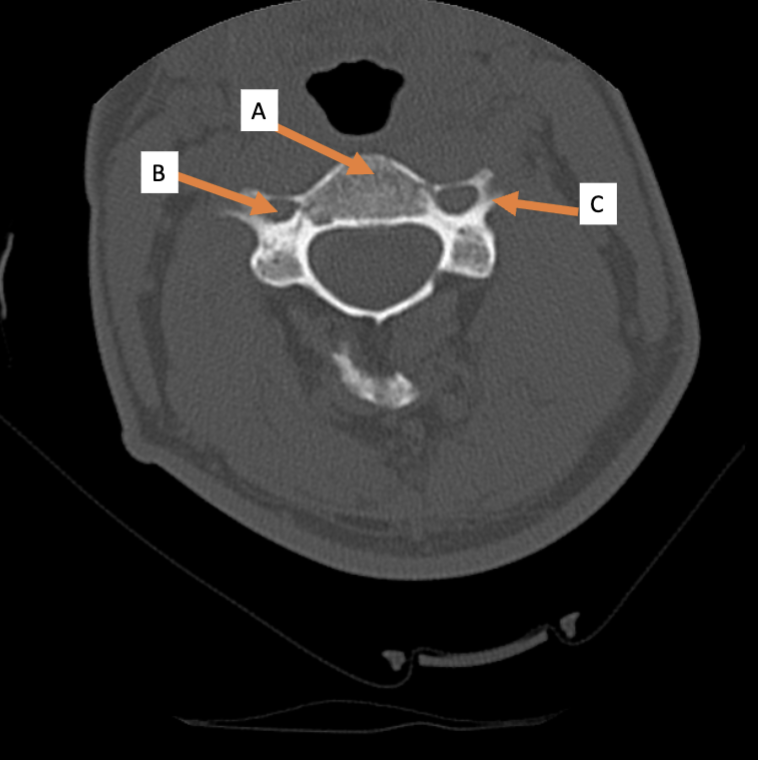

A. Identify structure

Transverse foramen; Vertebral a.

B. Identify structure; What goes through this feature?

Transverse process

C. Identify structure